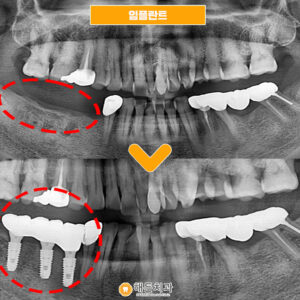

x-ray 사진을 촬영하여 검사해 보니,

차아 주변으로 까맣게 비춰 보이는 부분을

확인할 수 있었는데요,

치아 주변으로 염증도 생기고

뼈도 많이 녹아 있는 상태였습니다.

발치 후 임플.란트 식립을

도와드리기로 결정했답니다.

그리고 치아 발.치 후 회복이 되었을때

치아 뿌리 역할을 하는

임플란트 픽스처를 심어드렸답니다.

♥ 치료 전/후 ♥

(2024.01.25 ㅡ> 2024.06.10)

2개의 부위 모두

임플란트 식립을 완료한 모습입니다.

왼쪽 위의 치료는 마무리 되었고,

오른쪽 아래는

현재 픽스처만 심겨져 있는 상황인데요.

픽스처가 잇몸뼈에 단단하게 고정되고 나면

치아 머리 역할을 하는

크라운(보철물)을 올려

치료를 마무리 해 드릴 예정입니다. ^^